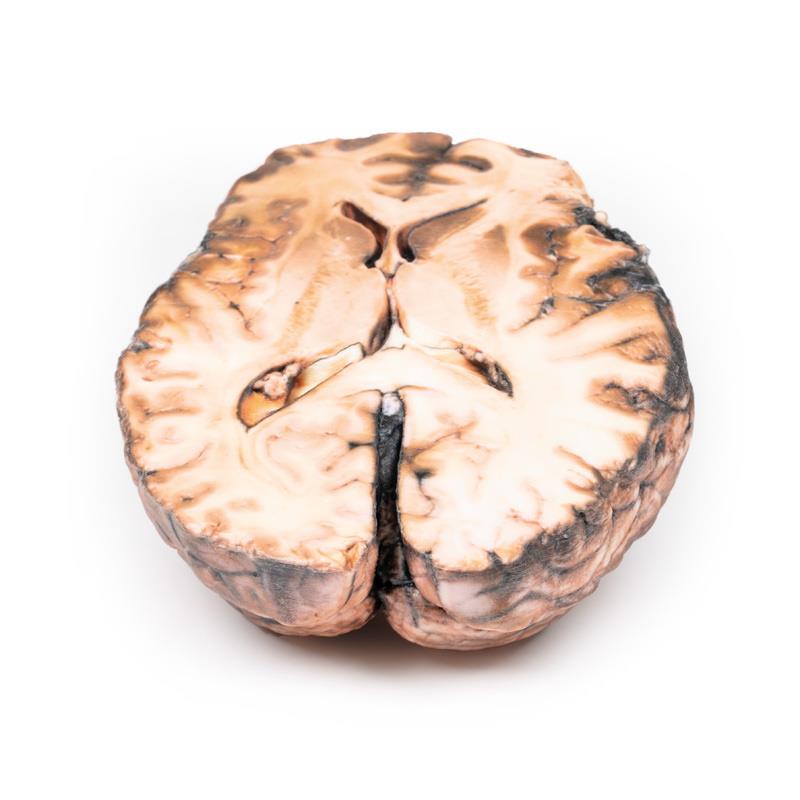

Patología: La muestra muestra la superficie basal del cerebro. Hay un aneurisma sacular de 5 mm de diámetro en la unión de la carótida interna derecha y la arteria comunicante posterior, que se ha roto. Hay sangre subaracnoidea en el área inmediata en la cisterna magna y en la superficie inferior del lóbulo frontal derecho. Hay un aneurisma intacto similar en el lado izquierdo. El lóbulo frontal derecho parece más blando y friable en la parte anterior